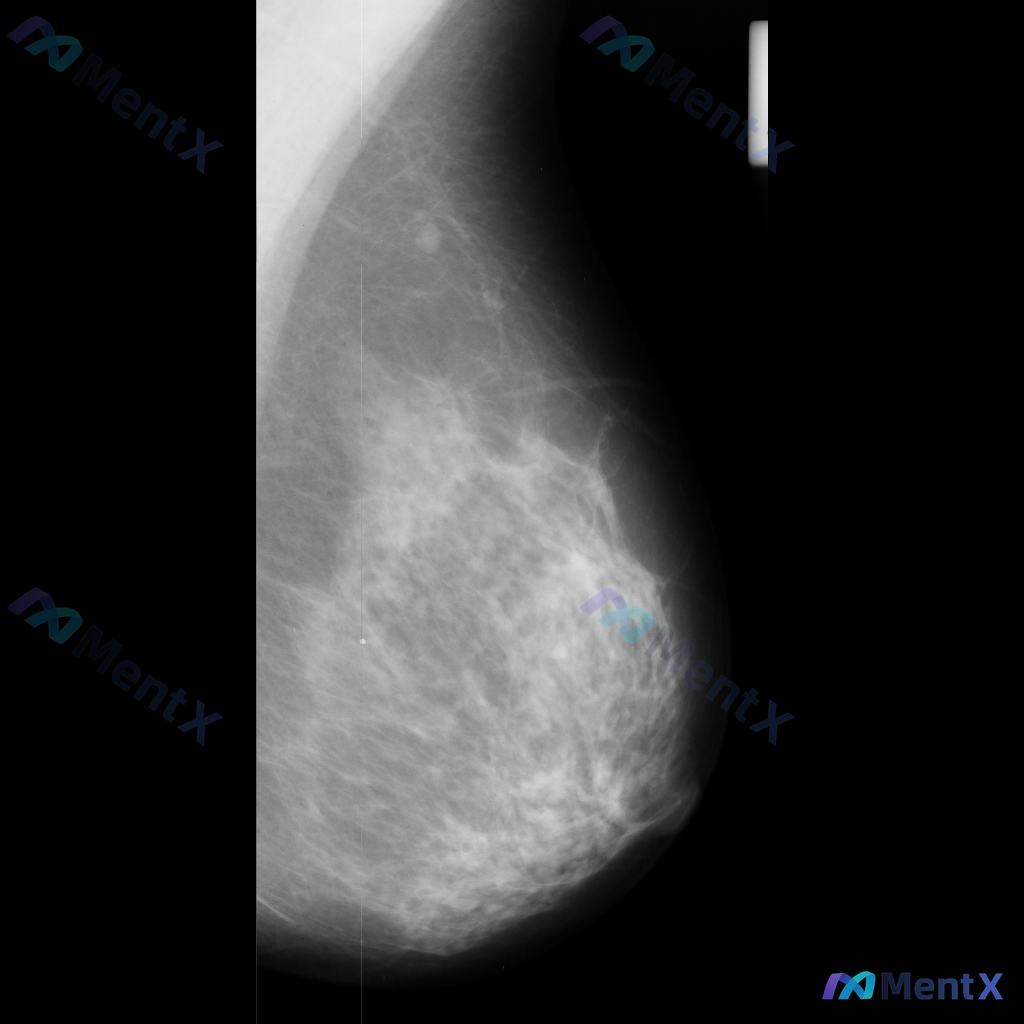

整理到一张单侧乳腺钼靶影像的读片资料,目前是单一体位图像,没有双侧对比。 影像表现整理 - 乳腺组织密度较高,属于多量腺体型或致密型背景 - 可见散在的钙化灶:图像中部偏下有数个点状或粗大钙化,形态不规则,但无典型恶性钙化的细小多形性、线样或分支状表现 - 乳腺下象限可见多个高密度圆形/卵圆形影,边...